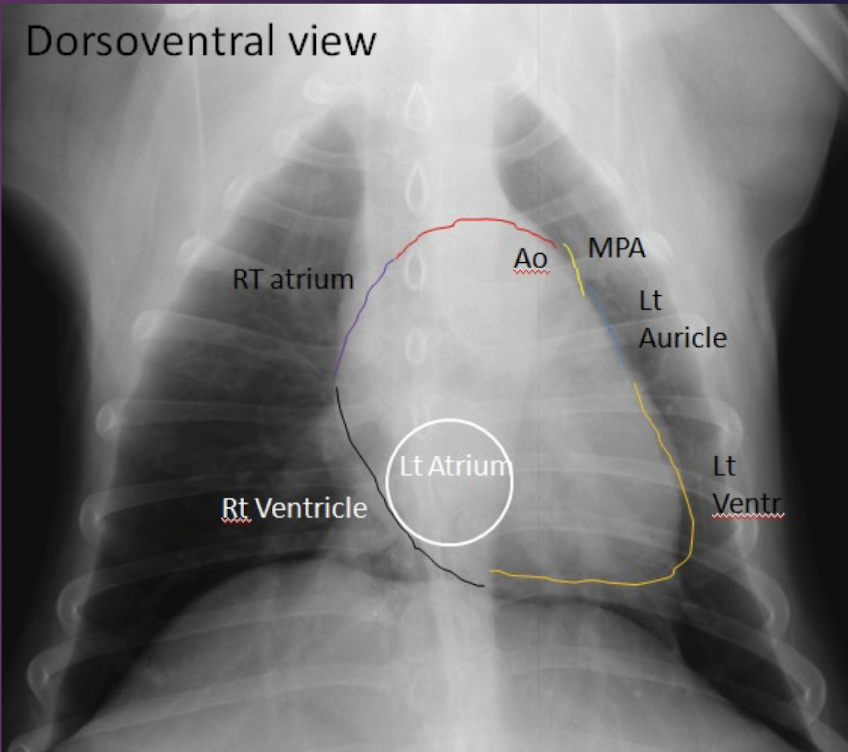

Factors of Dorsalventral Thorax (DV)

A

-only one hump is seen in diaphragm

-diaphragm is more cranial, pushes the tip of the heart to the left

-heart is more rounded(b/c of upright position)

-Caudal lobar vessels easier to evaluate(magnified, more perpendicular to x-ray beam and surrounded by more aerated lung)

-Accessory lung lobe less aerated due to more cranial position of diaphragm

Clock-face analogy for DV/VD

11-1–> Aorta

1-2–> Main Pulmonary artery

3–> Left Auricle

2-5–> Left ventricle

5-9–> Right Ventricle

9-11–> Right atrium

Left atrium is @ tracheal bifurcation